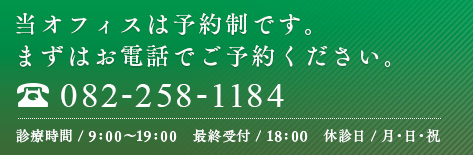

右上第一大臼歯部分にストローマン ピュア セラミック インプラント の埋入計画をCTシミュレーションします。

ジルコニア製インプラントはアバットメントまでをワンピースで構成しているため

2ピースインプラントよりも埋入位置の正確性が求められます。

模型とCTデータを重ねて埋入ポジションを決定します。